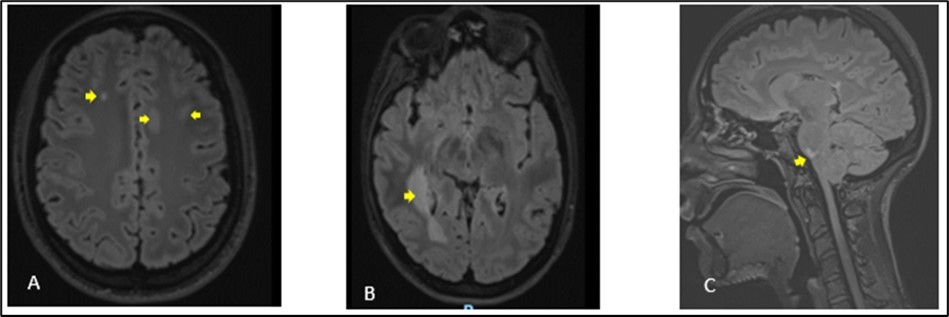

Figure 1.Cerebral MRI in FLAIR sequences showing multiple hyperintense lesions at the supratentorial (A, B) and infratentorial (C) levels. The largest supratentorial lesion (B) is opposite the right paraventricular white matter, at the level of the posterior horn and measures 55 x 17 mm axially. Presence of a lesion of pons (C) of 6.5 mm.

A 27-year-old girl presented at the emergency department, at a hospital in the Paris region on March 9, 2020 with complaints of left interscapular pain, paresthesias and weakness in the ipsilateral upper limb. These symptoms followed paresthesias on the fingertips of her right hand the day before her admission. She did not report fever, sphincter disorder or gait disturbance. No eye symptoms reported. In her medical history, she was treated two weeks earlier for pneumonia with COVID-19. There was no another previous infectious episode apart from the COVID-19. She had no history of diabetes, hypertension, cerebrovascular disease or migraine. She had not history of multiple sclerosis or Neuromyelitis Optica Spectrum Disorder (NMOSD). There was no history of smoking, contraception drugs intake or any prolonged drug intake. On the first examination in the neurology department where she was transferred on the same day of her admission, she had good general condition and was apyretic. She had a pulse rate of 74/min and the blood pressure was at 130/80 mmHg. The neurological evaluation showed on the left side, a muscular weakness grade 4 in the proximal part and grade 3 in the distal part of upper limb, and in the lower limb, the weakness graded at 3 in the distal part, using the Medical Research Council Scale (MRC) for muscle strength. There was no weakness on the right side. Deep tendon reflexes in both left and right were normal. Babinski sign was found on the left side. She presented tactil and algic hypoesthesia in the lower left limb ascending until the C4 level in the left side. There was no perineal sensitive trouble. The remain neurological exam including, higher functions, cranial nerves, was with no particularity. Otherwise, cardiovascular and respiratory systems examination were within normal limits. Blood laboratory tests were within the normal ranges, including complete blood count (CBC), C-Reactive protein, renal and liver functions and blood serum ionogram. Human Immunodeficiency Virus (HIV) tests including p24 antigen and antibodies to HIV were negative. Syphilis serology and Aquaporin 4 antibody were also negative. Encephalic Magnetic Resonance Imaging (MRI) demonstrated scattered hyperintense lesions on FLAIR imaging in deep hemispheric and juxtacortical white matter in supratentorial and in infratentorial floors (Figure 1). Medullary MRI showed T2 hyperintense lesions in left cervical hemi-marrow extending from C3 to C6, at T3, T4, T11 and T12 levels (Figure 2). These lesions were not enhanced after injection of gadolinium. The Cerebrospinal fluid (CSF) appeared to be colorless and clear with no cell detected microscopically; cerebrospinal protein level, 0.4 mg/L, glucose (Glu) level, 3.2 mmol/L; and instant blood glucose level, 5.2 mmol/L. CSF bacterial culture demonstrated no growth after 3 days, and herpes simplex virus 1 and 2, varicella-zoster virus test was negative. Reverse transcription-polymerase chain reaction (RT-PCR) assay test for COVID-19 was negative in the CSF. The final diagnosis was an ADEM secondary to novel coronavirus (nCov) infection. She was given methylprednisolone (1000 mg IV per day for 5 days) followed by Intravenous Immunoglobulin (IVIG) therapy at 0.4 g/kg daily for 5 days. Together with chemotherapy, she received physiotherapy coupled with occupational therapy. The outcome was good with improvement of weakness and paresthesias. There was residual tingling on the fingertips of the left hand. The patient was discharge on day 13.